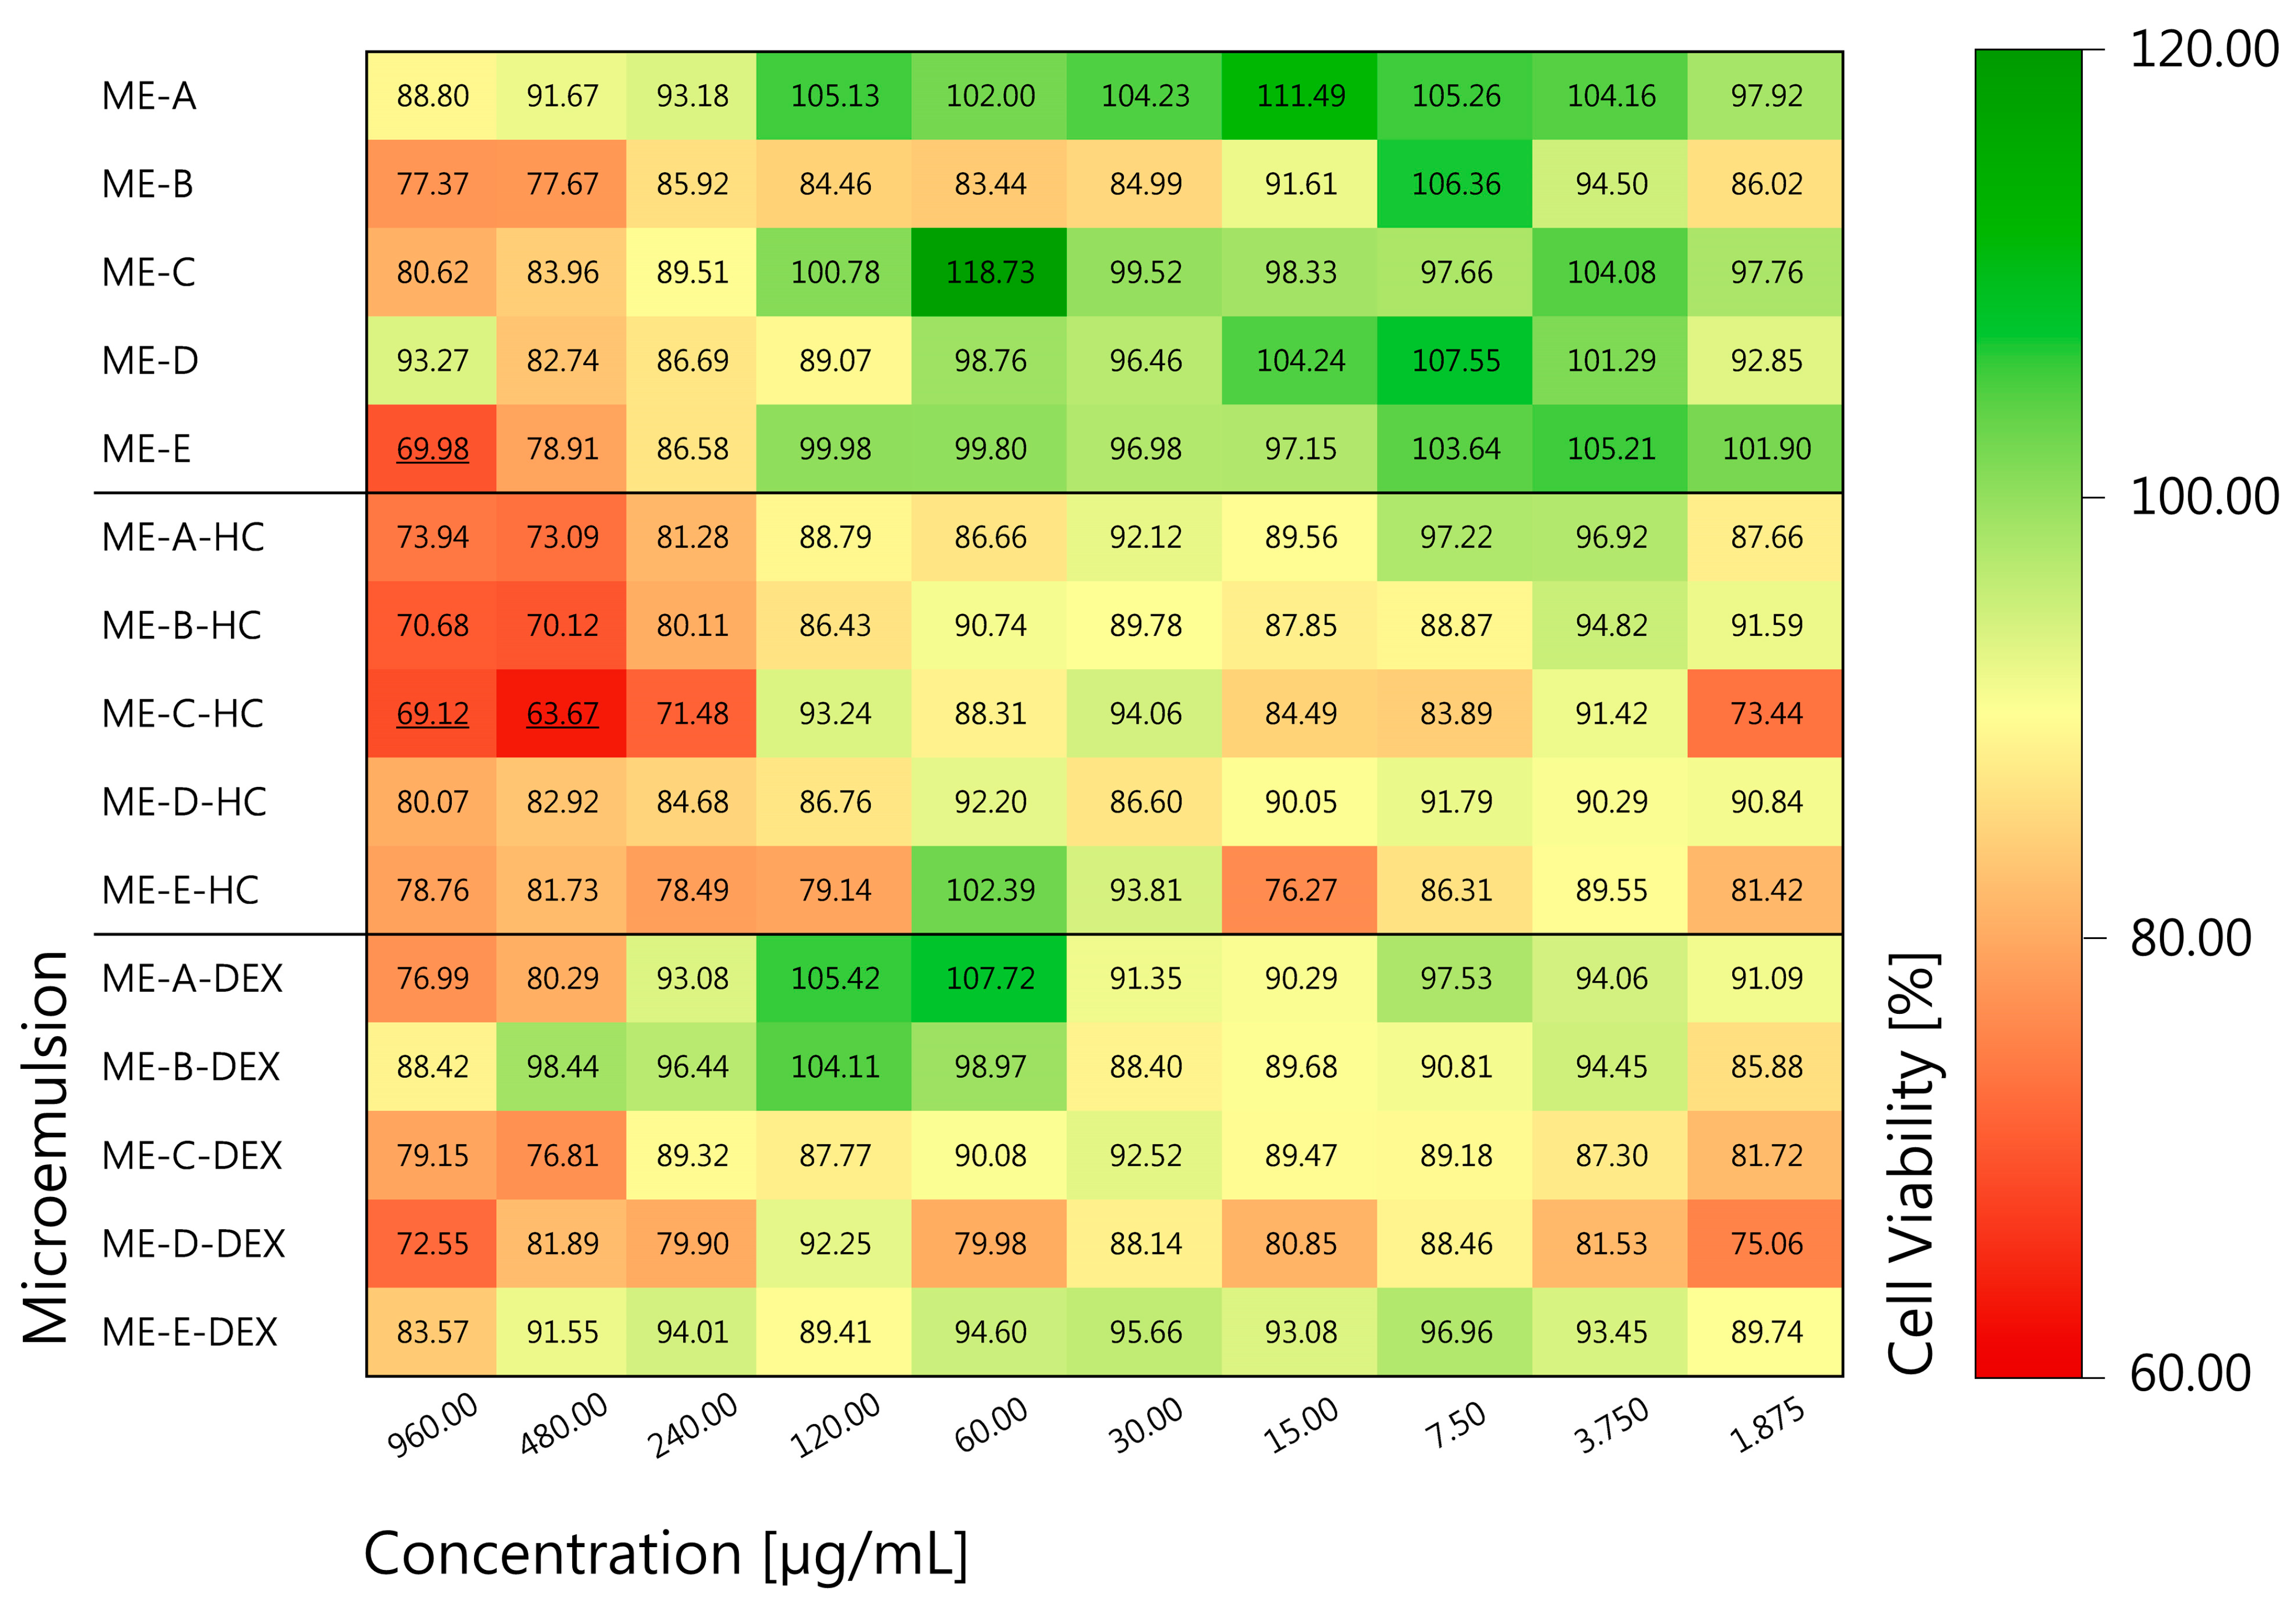

3.1.4. In Vitro Cytotoxicity